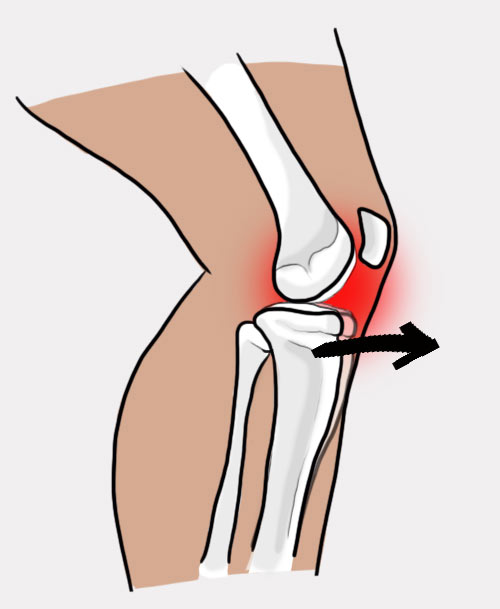

Uraz najczęściej występuje w wyniku wymuszonego tylnego przemieszczenia piszczeli. Do rozerwania PCL jest konieczna duża siła, dlatego bardzo często przyczyną urazu są wypadki samochodowe, gdzie dochodzi do uderzenia kolanem o deskę rozdzielczą.

Uraz najczęściej występuje w wyniku wymuszonego tylnego przemieszczenia piszczeli. Do rozerwania PCL jest konieczna duża siła, dlatego bardzo często przyczyną urazu są wypadki samochodowe, gdzie dochodzi do uderzenia kolanem o deskę rozdzielczą.

Orteza kolana RAPTOR/2RA stabilizuje staw w płaszczyźnie strzałkowej i czołowej. Orteza RAPTOR/2RA posiada 4-punktowy system podparcia, który doskonale stabilizuje i odciąża staw kolanowy. W przypadku uszkodzonego więzadła krzyżowego tylnego (PCL), kość piszczelowa ma tendencję do nadmiernego przemieszczania się w kierunku tylnym względem kości udowej. Konstrukcja przednio-tylna ortezy pozwala na zabezpieczenie piszczeli i ustawienie jej w osi stawu kolanowego.

W przypadku uszkodzonego więzadła krzyżowego tylnego (PCL), kość piszczelowa ma tendencję do nadmiernego przemieszczania się w kierunku tylnym względem kości udowej. Konstrukcja przednio-tylna ortezy pozwala na zabezpieczenie piszczeli i ustawienie jej w osi stawu kolanowego.